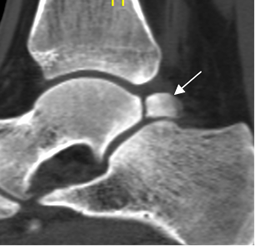

Fig 100. Pinzamiento posterior por proceso de Stieda.

A: Rx lateral. Presencia de proceso de Stieda.

B: RM sagital en STIR. Proceso de Stieda que produce pinzamiento y signos de sinovitis.